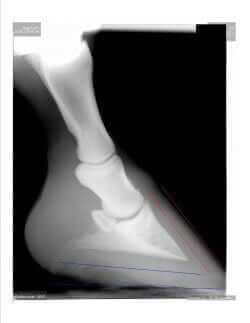

What we do know is that in cases of laminitis, there is a disruption of blood flow to the laminae, which in turns impacts the overall tissue health. As the tissue becomes impacted, the level of attachment or integrity degrades and the coffin bone is not longer held rigid in position. Under normal conditions, when viewing an X-ray, the front edge of the coffin bone should be relatively parallel to the front of the hoof wall. In cases of laminitis, the laminar health degrades and the coffin bone begins to rotate downward due to weight of the animal as well as backward pull of the deep flexor tendon. In this image, one can see two important points. First, the front of the coffin bone is relatively parallel to the hoof wall and second (red lines), the palmar aspect or bottom of the coffin bone should have a slight angle to the floor or bottom of the hoof wall. (Blue Lines) The coffin bone should not, in ideal circumstances, be parallel to the ground surface.

Now, this image is not ideal, because actually this horse had low grade signs of laminitis due to a couple of other anatomical issues. First, this horse has too long of a toe, which contributes to a fulcrum type of effect and is common in laminitic horses due to chronic changes in hoof growth. Second, the alignment of P1, P2 and P3 has a somewhat concave shape. Ideally, these three bones should be in a straight line type of alignment. This type of concave can actually predispose to degenerative joint changes, such as ringbone, which is actually present in a non-articular fashion in this horse’s coffin joint.